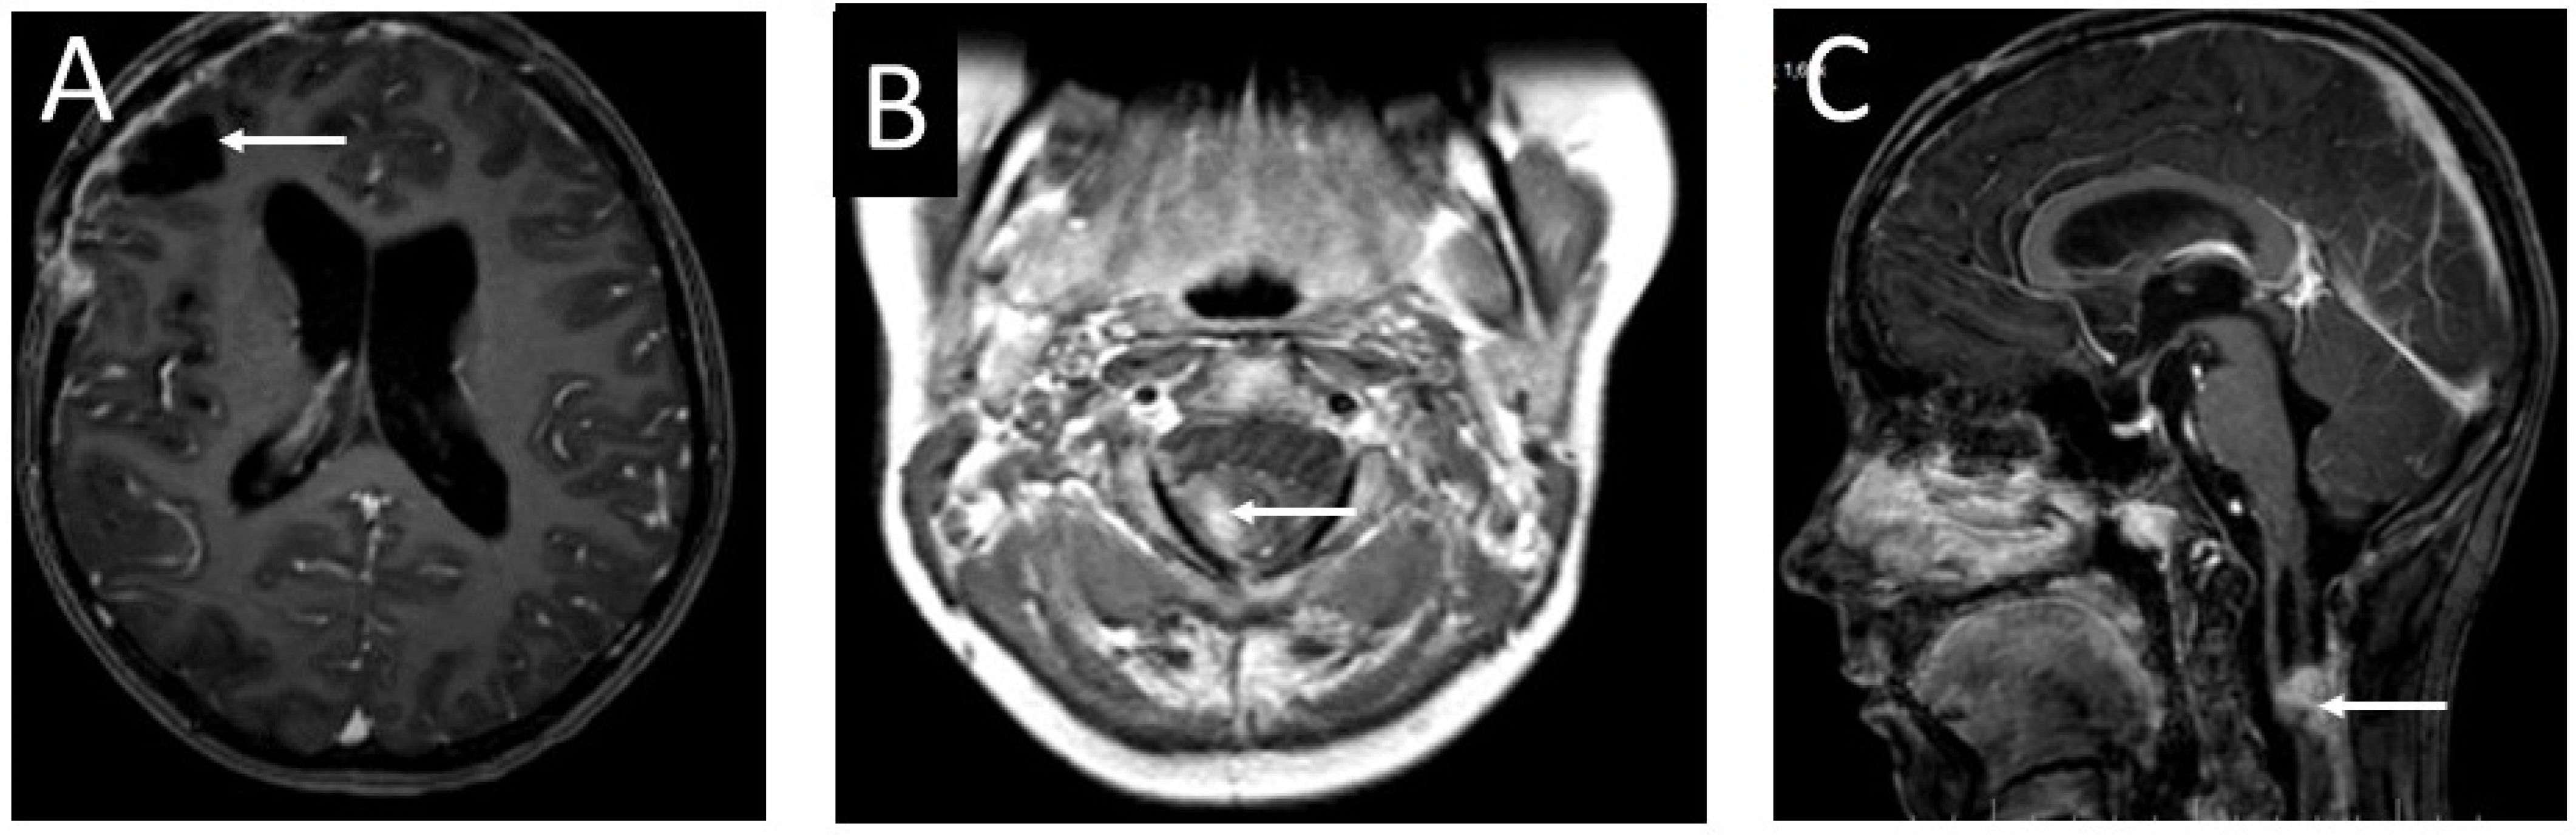

The patient was referred to an oncological center for further diagnosis and treatment. The child underwent dermatoscopy and two skin birthmarks were selected for removal (Figure 2). A histological examination did not show any malignant transformation in the analyzed samples. The child was qualified for stereo-radiotherapy. Three months later, the patient developed hydrocephalus and required shunt implantation. The biphasic MRI showed no metastases in the subarachnoid space and no progress of the residual cervical spine tumor (Figure 10). After discharge from hospital, the girl underwent chemotherapy.

Figure 10.

Contrast-enhanced T1 MRI images of the head and cervical spine of the 13-year-old girl before the valve implantation: (A) an axial section of the head. The photo does not show progression of the tumor (arrow). (B) MRI of the cervical spine—an axial section. Visible remnants of the tumor diagnosed as melanocytoma (arrow). (C) An MRI—sagittal section of the cervical spine. The residual tumor mass shows no enlargement compared to previous diagnostic images (arrow).